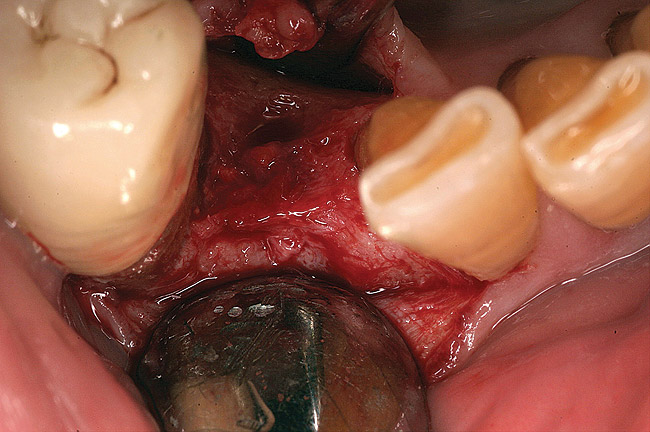

Thirty patients were selected on the basis of need for dental extractions with bone preservation and/or augmentation in the socket before the placement of a dental implant. These patients were cleared medically for oral surgical procedures. Preoperative clinical photographs and periapical radiographs were taken. After administration of local anesthesia, full-thickness labial and lingual/palatal flaps were elevated. Minimal soft-tissue manipulation was performed to allow visualization of the entire alveolar crests and debridement of fenestrations and/or dehiscence defects, if present. Elevation of each tooth or retained roots was performed, using periotomes, luxatomes, proximators, root forceps, and any other instruments and procedures as required to extract the tooth with minimal trauma (Figure 1). After extraction and thorough debridement of the socket by mechanical means, clinical photographs were taken. The sites then were grafted with a resorbable β-TCP of small particle size, 150 µm to 500 µm (Cerasorb) (Figure 2). This material has been used and reported in the literature for almost 30 years as a viable bone graft in orthopedic and other surgical specialties. In this study, the granules of β-TCP were mixed thoroughly with blood from the surgical sites and the sockets filled to ideal contours faciolingually and apicocoronally. The grafts and adjacent 3 mm of alveolar bone then were covered with resorbable collagen barriers (BioMend®, www.zimmerdental.com) (Figure 3). The flaps were repositioned and the areas closed with an appropriate number and type of sutures. No attempts were made to obtain primary closure over the exposed barriers. Postoperative radiographs and clinical photographs were taken. Subsequently, sutures were removed at 1 to 2 weeks.

The grafted sites were followed clinically and radiographically throughout the healing period. Healing of the residual crestal defects (if present) also was followed. At approximately 6 months, the patients returned for graft analysis and placement of implants. Clinical photographs and radiographs were taken preoperatively. After administration of local anesthesia and minimal flap elevation, measurements of alveolar ridge width were repeated to compare with the preoperative alveolar dimensions (Figure 4). The coronal portions of the regenerated sites were evaluated for the presence of residual graft material. Preparation of the osteotomies was initiated with a bone trephine to sample the coronal 5 mm to 7 mm of socket healing (Figure 5). The placement of appropriately sized dental implants was performed according to the manufacturer’s recommendations, and the flaps were sutured to facilitate both soft- and hard-tissue healing.

Figure 2  The extraction socket was grafted with a mixture of pure-phase β-TCP and heme from the surgical site.

Figure 2

Figure 3  A resorbable collagen barrier was placed over the graft material for particle containment and guided bone regenerative principle.

Figure 3

Figure 13  After debridement of the socket, a mixture of pure-phase β-TCP and heme from the surgical site was covered with a dense polytetrafluoroethylene (PTFE) barrier.

Figure 13